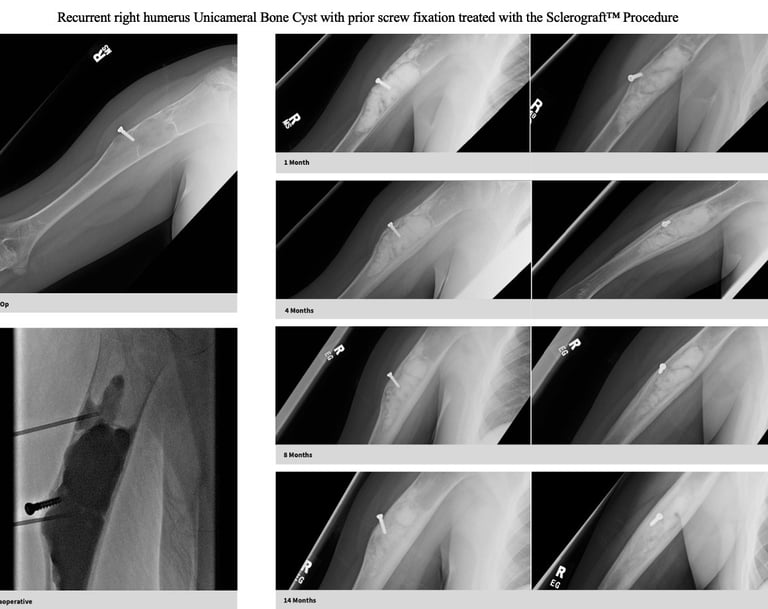

Gallery

Explore our educational resources and images